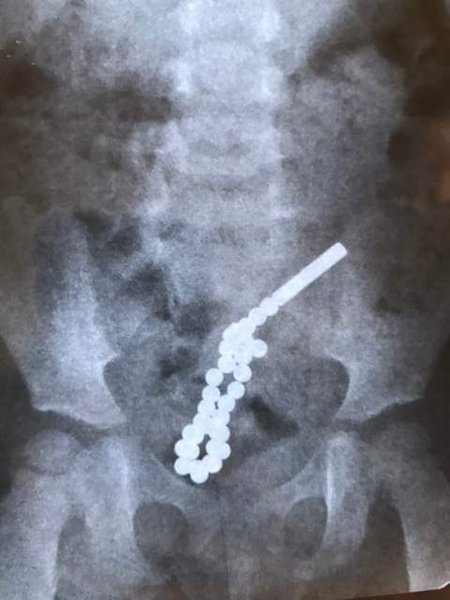

Хирурги львовской городской детской больницы срочно прооперировали двухлетнюю девочку, которая проглотила 31 неодимовый магнит в виде шариков. Попав в разные петли кишечника, эти очень сильные магниты начали притягиваться друг к другу и пробили кишечник ребенка в семи местах. Операция по спасению продолжалась почти два часа.

Как сообщил детский хирург Дмитрий Грицак, девочке 2 года и семь месяцев. В больницу она поступила с жалобами на боль в животе. Рентген показал, что ребенок проглотил магнитные шарики, которые попали в кишечник.

рентген, снимок, кишечник, ребенок, магниты, шарики